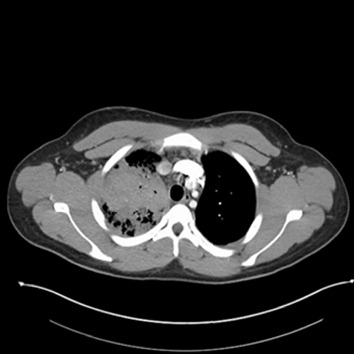

背景:电子烟的使用在年轻人中越来越普遍,这引起了人们对其潜在健康影响和感染易感性的担忧。枯草芽孢菌,芽孢菌病的病原体,是一种二态真菌地方性的某些地区的美国。我们报告了一例罕见的肺芽孢菌病,发生在一名长期使用电子烟的年轻免疫功能正常的男性患者身上,强调了在有呼吸道疾病危险因素的患者中,在鉴别诊断病因不明的肺炎时考虑真菌感染的必要性。症状:20岁男性,4年每日使用电子烟,职业为排水沟清洁工,10天咳嗽加重、痰血、呼吸短促、盗汗、发烧和体重减轻。他血流动力学稳定,需要最低限度的氧气支持,胸部x线片显示右上肺叶肺炎和空洞病变。患者接受了社区获得性肺炎、非典型肺炎、肉芽肿性疾病以及免疫抑制和病毒性淋巴细胞增生性疾病的检测。诊断性支气管镜检查最终确诊为芽菌病,并给予两性霉素B和伊曲康唑治疗,临床明显改善。结论:肺芽孢菌病多无症状表现,重症多见于老年人或有合并症和免疫功能障碍者。医生往往忽视它作为原发性肺部感染的鉴别诊断,关注年轻人的细菌性肺炎和结核病。这一案例强调了进一步调查电子烟使用对免疫功能影响的必要性。考虑到芽孢菌病的发病率不断上升,以及在整个州发生的广泛的建筑和土壤破坏,该病例还突出了使芽孢菌病成为格鲁吉亚一种可报告疾病的重要性。

Background: E-cigarette use has become increasingly prevalent among young adults, raising concerns about its potential health impact and susceptibility to infections. Blastomyces dematitidis, the causative agent of blastomycosis, is a dimorphic fungus endemic to certain regions of the United States. We present a rare presentation of pulmonary blastomycosis in a young, immunocompetent male with chronic e-cigarette use, highlighting the need to consider fungal infections in the differential diagnosis of pneumonia of unknown etiology in patients with risk factors for respiratory illness. Presentation: A 20-year-old male with a 4-year history of daily e-cigarette use and gutter cleaner by occupation presented with a 10-day history of worsening cough, bloody sputum, shortness of breath, night sweats, fever, and weight loss. He was hemodynamically stable, required minimal oxygen support, and was admitted for chest X-ray showing right upper lobe pneumonia and cavitary lesion. The patient was tested for community-acquired pneumonia, atypical pneumonia, granulomatous diseases, and immunosuppressive and viral lymphoproliferative disorders. A diagnostic bronchoscopy ultimately confirmed blastomycosis, leading to treatment with amphotericin B and itraconazole, resulting in significant clinical improvement. Conclusion: Pulmonary blastomycosis often presents asymptomatically, with severe cases more common in the elderly or those with comorbidities and immune dysfunction. Physicians tend to overlook it as a differential diagnosis for primary lung infections, focusing on bacterial pneumonia and tuberculosis in younger individuals. This case underscores the need for further investigation into the impact of e-cigarette use on immune function. This case also highlights the importance of making blastomycosis a reportable disease in Georgia, considering its increasing incidence and the widespread construction and soil disturbance occurring throughout the state.